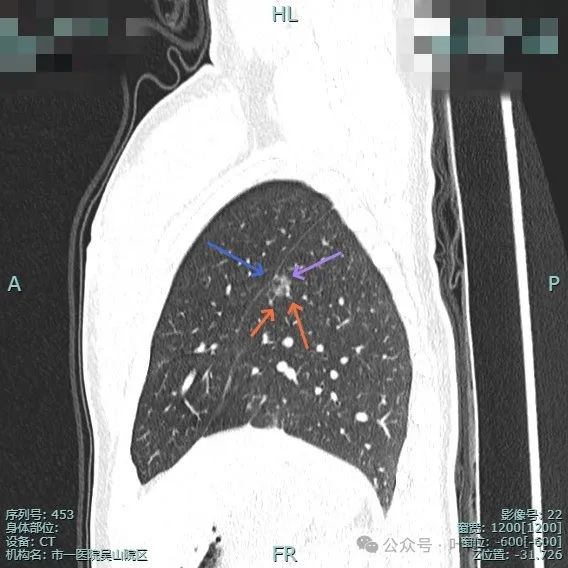

再看主要病灶的靶重建情况:

左侧病灶10:

病灶表面不平有分叶与凹凸,密度也不均匀,有点状实性成分,邻近胸膜(叶间裂)。

表面有毛刺,灶内有小空泡征,边缘毛糙不平,密度显得不均匀。

部分边缘有毛刺或小棘突,病灶边上有扩张的细支气管,整体内部密度欠均匀。